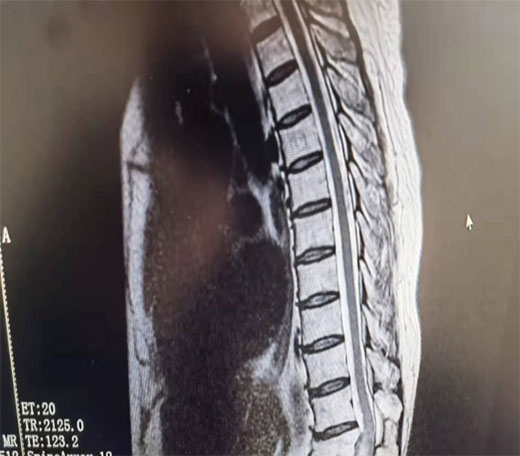

术前资料

该患者曾到多家医院就诊,当椎间盘突出或腓总神经损伤治疗,针灸理疗、拔罐、吃药都不见好转,遂到我科就诊住院。我科经讨论后认为,有可能是椎管内占位,遂给予核磁检查,果真发现胸12椎管内有一“胡豆”大的肿瘤,椎管内位置狭小,脊髓已严重受压,已出院不全瘫痪症状,情况十分危急,必须行肿瘤切除手术。经骨伤科和医院相关科室专家讨论,认为手术风险巨大,很可能出现手术后神经症状加重,甚至导致完全瘫痪,而我院并无相关处理经验,仅多年前请上级医院专家做过类似手术,故建议患者转上级医院或请省里的专家来院做手术。而患者家庭贫困,听说要转院或请专家来做手术,花费比较大,要求出院放弃治疗。患者说:“我都快七十岁了,治好了也挣不了那些钱,回去了养养能好就好,不能好就这样了”。骆渊城副院长得知相关情况后,再次组织科内讨论,一致认为,不做手术必将瘫痪,放手一搏还有希望。遂与患者沟通后决定就在骨伤科手术,并成功在显微镜下完整切除了肿瘤。